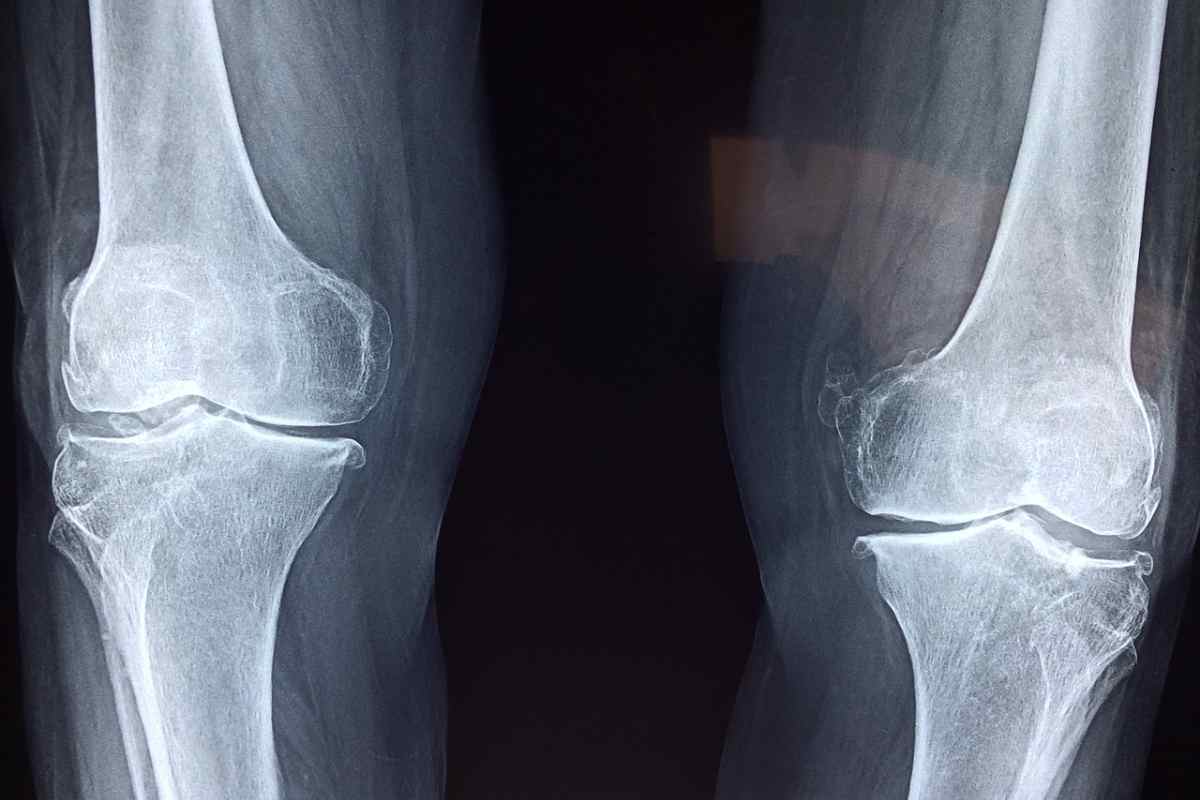

Pinturault sarà costretto a saltare i Mondiali di Salbaach, in programma dal 4 al 16 febbraio. La diagnosi, infatti, è di quelle pesanti: vasta contusione ossea del piatto tibiale interno, con associata frattura e lesione al menisco interno. La notizia per così dire positiva è che non risulta essere stato danneggiato il legamento crociato anteriore.